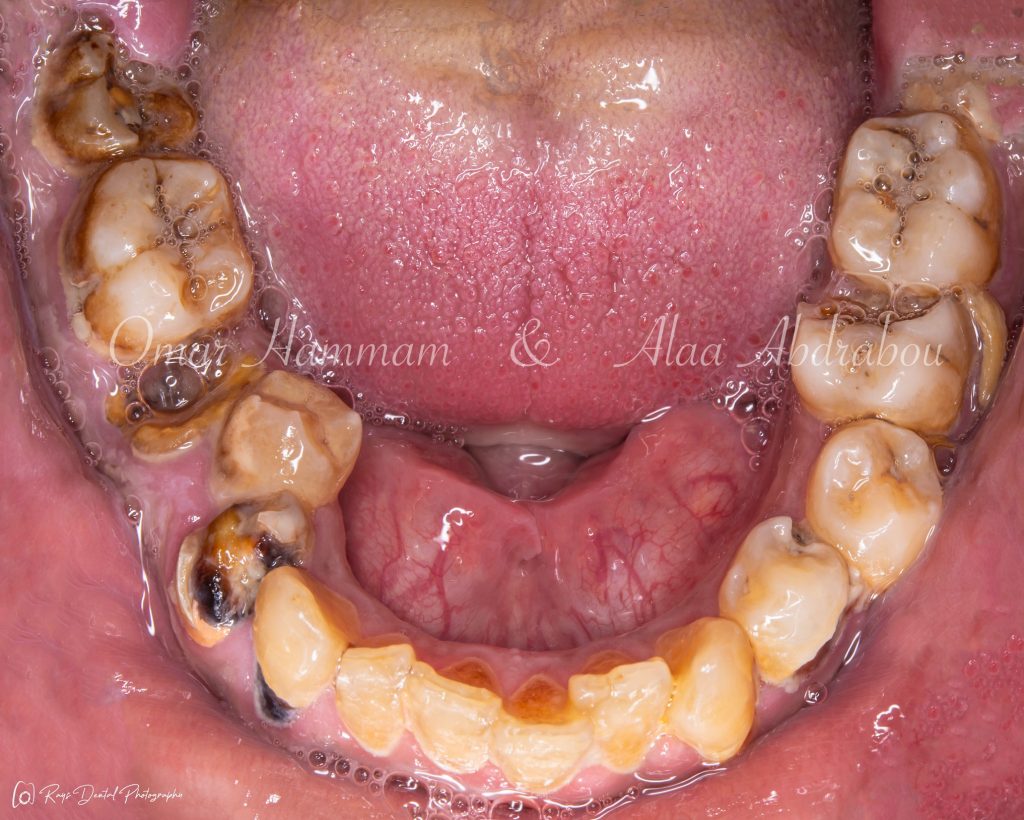

📕 𝑷𝒂𝒓𝒕 1 (𝑪𝒍𝒊𝒏𝒊𝒄𝒂𝒍 𝒆𝒙𝒂𝒎𝒊𝒏𝒂𝒕𝒊𝒐𝒏 & 𝑫𝒊𝒂𝒈𝒏𝒐𝒔𝒊𝒔):

🔗 https://heyzine.com/flip-book/e610d6bc90.html